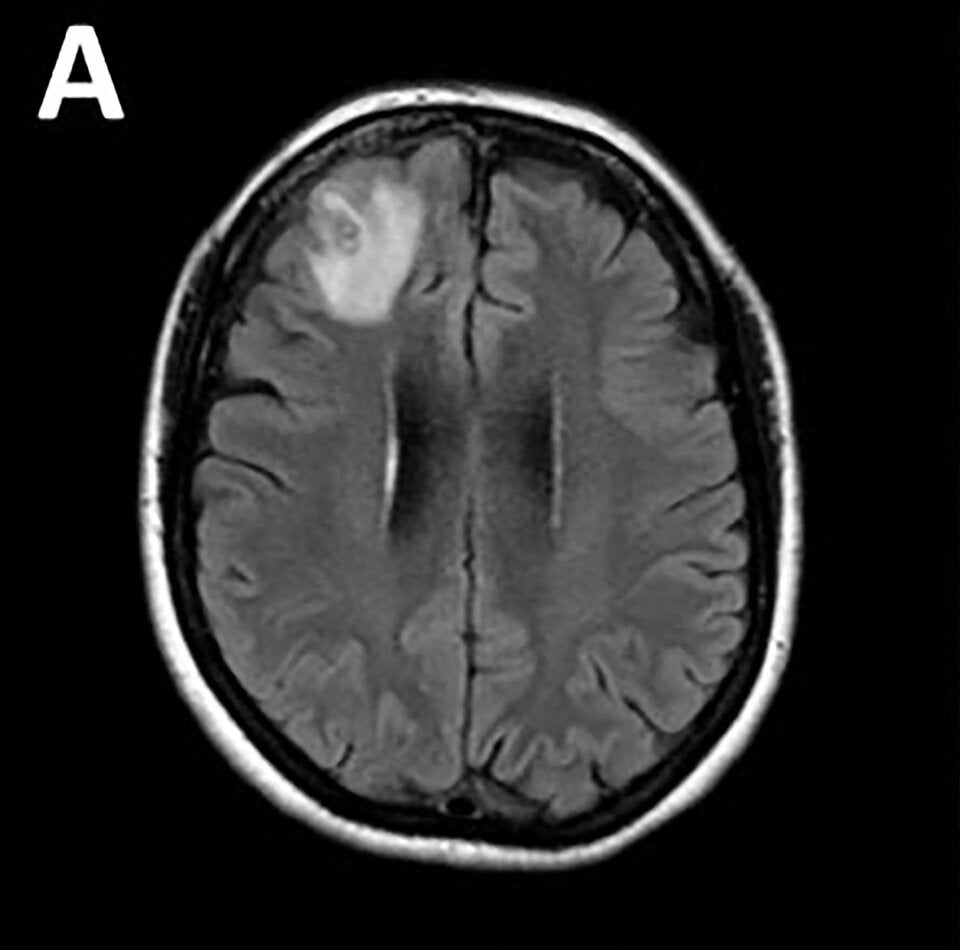

Die Patientin aus dem Bundesstaat New South Wales hatte Anfang 2021 zunächst über wochenlange Bauchschmerzen und Durchfall gefolgt von trockenem Husten und Nachtschweiß geklagt. Ein Jahr später gehörten auch Vergesslichkeit und Depressionen zu ihren Symptomen. Die Frau wurde daraufhin ins Krankenhaus von Canberra überwiesen. Eine MRT-Untersuchung ihres Gehirns ergab schließlich Anomalien, die eine Operation nötig machten.